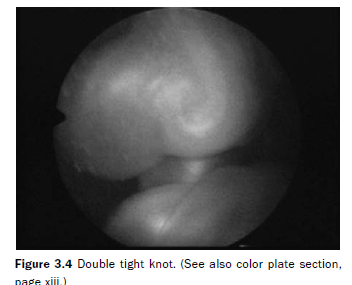

Indirect evidence in support of the facultative etiology comes from a selected group of cases in which the diagnosis of congenital heart disease is made in one of the fetuses. Almost invariably, the affected twin would be the recipient. Of 615 patients assessed at our institution, congenital heart disease was diagnosed in 6 fetuses (0.9%), mostly pulmonary artery stenosis (Table 3.3). An additional 3 patients had abnormalities of the umbilical cord, which presumably could also hinder blood return to the donor, or impair oxygenation in the recipient from obstruction of the umbilical vein, resulting in congestive heart failure of the recipient. One of the patients with cord abnormalities had a double tight knot (Figure 3.4). The other two patients had an umbilical cord kink. In all but one case, the fetus with either congenital heart disease or umbilical cord obstruction was the recipient.